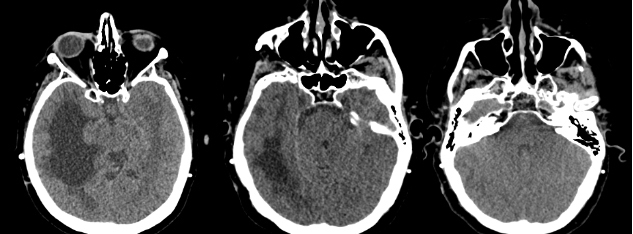

La patiente est hospitalisée, voici certains clichés de son imagerie cérébrale :

Figure 2 (source : S. Demortière)

Figure 3 (source : S. Demortière)

À noter : une imagerie médullaire récente est sans anomalie.

L’imagerie par résonance magnétique (IRM) cérébrale en pondération FLAIR montre un épaississement diffus des méninges évocateur d’une pachyméningite.